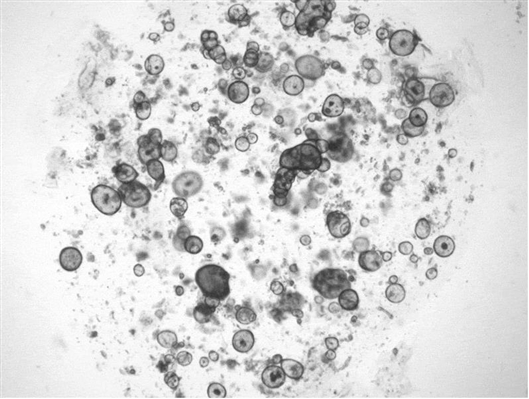

泪腺类器官因“眼泪”而膨胀。图片来源:Marie Bannier-Hélaou?t/Hubrecht Institute

由于类器官缺乏导管,“眼泪”的产生导致它们膨胀。“如果有一个小管道,就会有液滴。”Clever说。当研究小组将这些类器官移植到小鼠体内后,这些组合成熟并发育出了含有眼泪中蛋白质的管状结构。